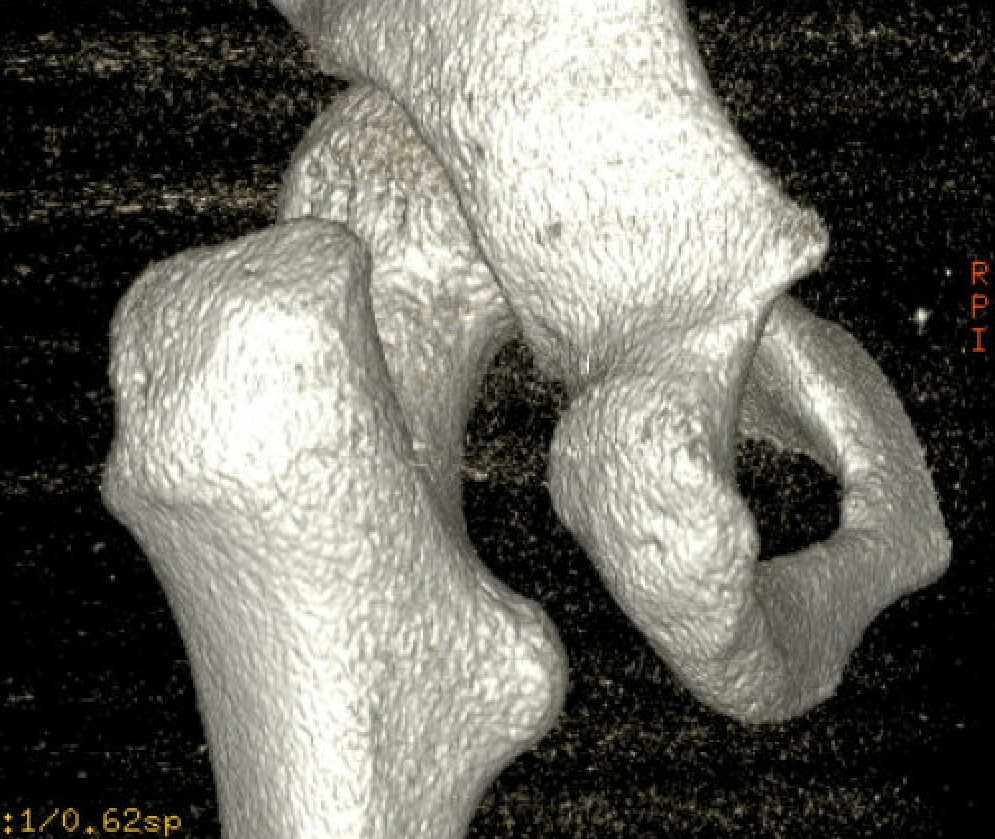

CT

Reduced ischiofemoral space - distance between the lesser trochanter and the ischial tuberosity

Reduced quadratus femoris space - distance between hamstring tendon and iliopsoas